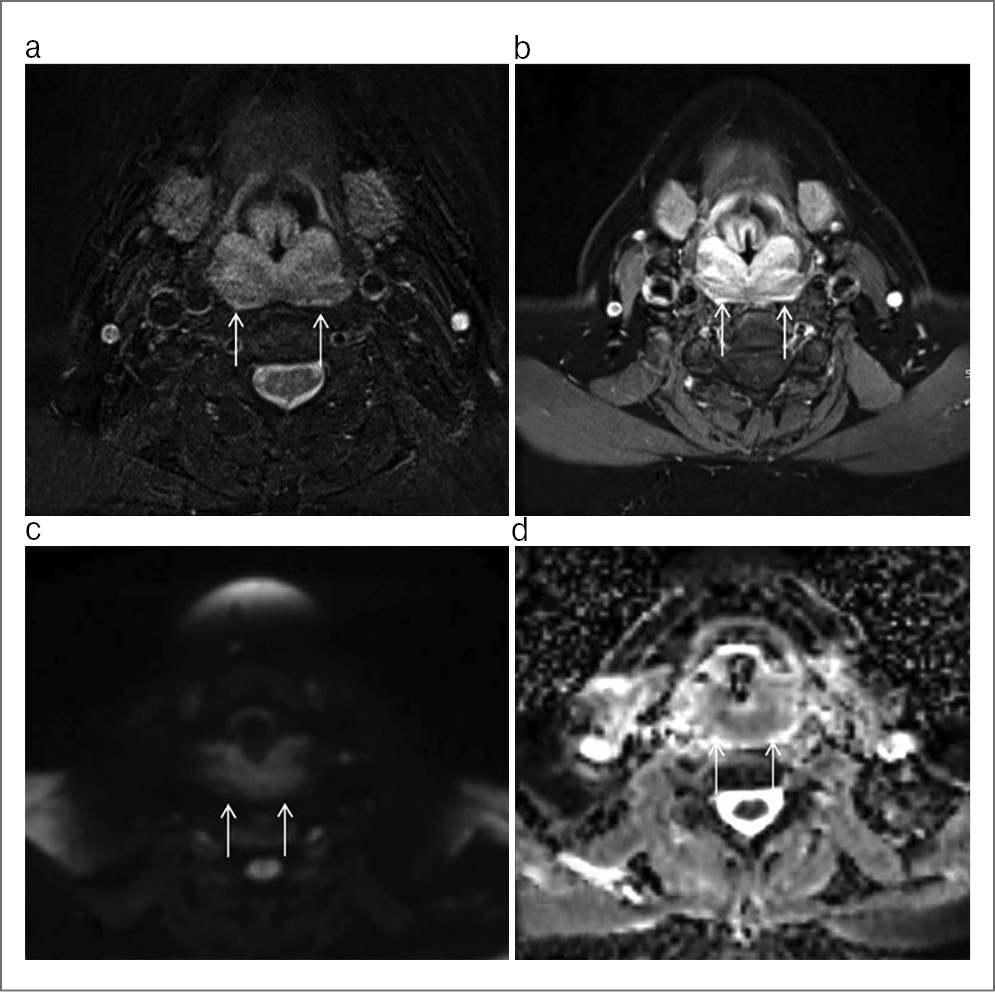

Пациент предоставил заключение врача-инфекциониста, данных о наличии герпесвирусной инфекции, инфекции, вызываемой вирусом Эпштейна–Барр, и цитомегаловирусной инфекции не получено. Пациенту назначена компьютерная и магнитно-резонансная томография околоносовых пазух для определения распространения патологического процесса, а также исключения инвазии в смежные анатомические области (рис. 2, 3). В предоперационном периоде под контролем эндовидеоскопического оборудования пациенту выполнен забор материала из свода носоглотки, верифицирован диагноз саркоидоза носоглотки (рис. 1, 4).

Рис. 3. Результаты магнитно-резонансной томографии околоносовых пазух у пациента с диагнозом саркоидоза носоглотки. Стрелками обозначен патологический процесс.